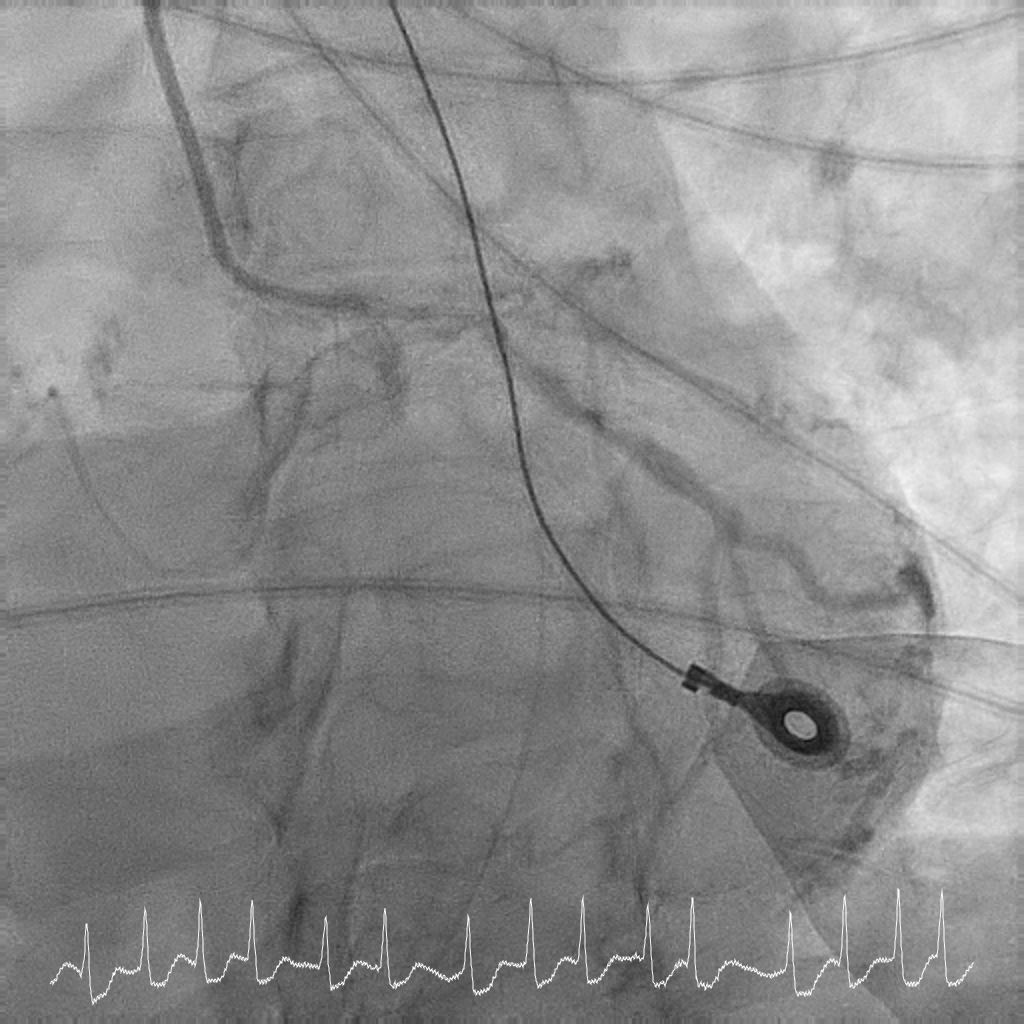

Coronary angiography showed critical calcified LM into both LAD and LCx. LAD was noted to be calcified and occluded at the ostium, with collaterals from LCx filling the distal LAD. RCA was a long segment CTO (occluded at the ostium) and showed retrograde filling from LCx collaterals. There was moderate proximal disease of the LCx. Cardiac surgery was consulted for consideration of urgent CABG, but surgical risk was prohibitive. After discussion with family, decision was for high-risk complex PCI.

Rotational atherectomy with 1.5mm and then 2mm was performedfrom ostial LM to proximal LCx. Wiring of the LAD was only successful till midLAD with a separate distal LAD occlusion. LAD lesion was balloon uncrossableand half-way rotational atherectomy with 1.5mm burr. The distal LAD CTO wasthen crossed and balloon angioplasty undertaken. There was diffuse LAD disease, and the plan was then for ahybrid strategy. PCI to LM bifurcation was secured using the DK crushtechnique. 3.5x23mm Xience Sierra was placed in the LCx, 3.5x16mm Megatron inLM to proximal LAD followed by drug coated balloon angioplasty for the rest ofthe LAD with 2x40mm, 2.5x40mm, and 3x25mm balloon. She recovered well after her intervention and is infunctional New York Heart Association Class I, Canadian Cardiovascular Society Angina Grade 0. An elective angiogram was performed 6 months after indexprocedure to re-assess the results. This showed widely patient stents acrossthe LM-LAD-LCX, and excellent DCB results across the proximal to distal LAD andimprovement of her left ventricular ejection fraction.